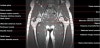

- Coronal section

T1 Allows for evaluation of both hips simultaneously even though the patient may be symptomatic in only one hip.

T2 allows for detection of abnormal fluid in both hips which may be seen in avascular necrosis, stress fractures, muscle tears or perilabral cysts.